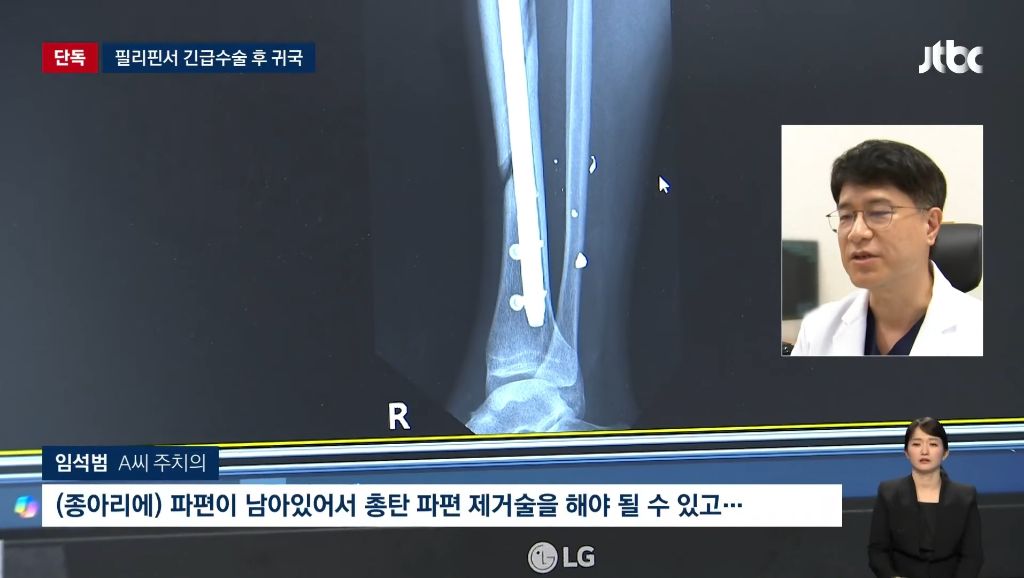

필리핀에서 한국인 관광객 총맞고 가방 빼앗겨

다행히 죽진않았음